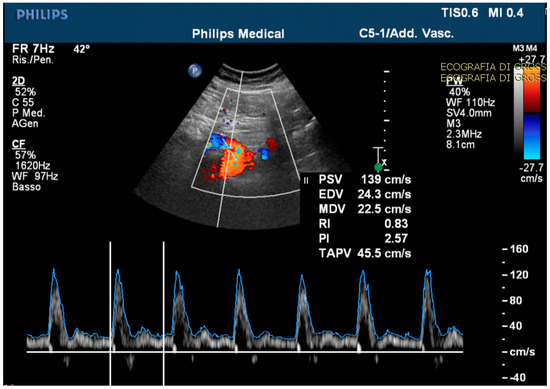

Routine and specific blood and stool tests (according to the diseases’ epidemiology in our region, Sardinia, Italy) for hepatic, pancreatic, intestinal, infectious, celiac, autoimmune, and hematological diseases showed normal results. The upper endoscopy and colonoscopy were negative for significant findings. Interestingly, in the ultrasound scan of the abdomen cavity, we noticed agenesis of the left hepatic lobe, splenomegaly, and enlargement (1.89 cm at the ostium and 1.53 cm downstream) of the CMT (normally ranging between 0.7 to 1 cm) (Figure 1).

Figure 1.

The celiac-mesenteric trunk observed by an ultrasound scan of the abdomen, indicating the size of the proximal and distal site.

The echo-color-Doppler revealed a high resistance flow in the proximal site of the CMT (Figure 4).

Figure 4.

The echo-color-Doppler detected a high resistance flow in the proximal site of the celiac-mesenteric trunk, usually ranging from systolic velocity peaks between 90–100 cm/s (PSV); 30–65 cm/s end diastolic velocity peaks (EDV); and a pulsatility index (PI) of 1.5 ± 0.02.